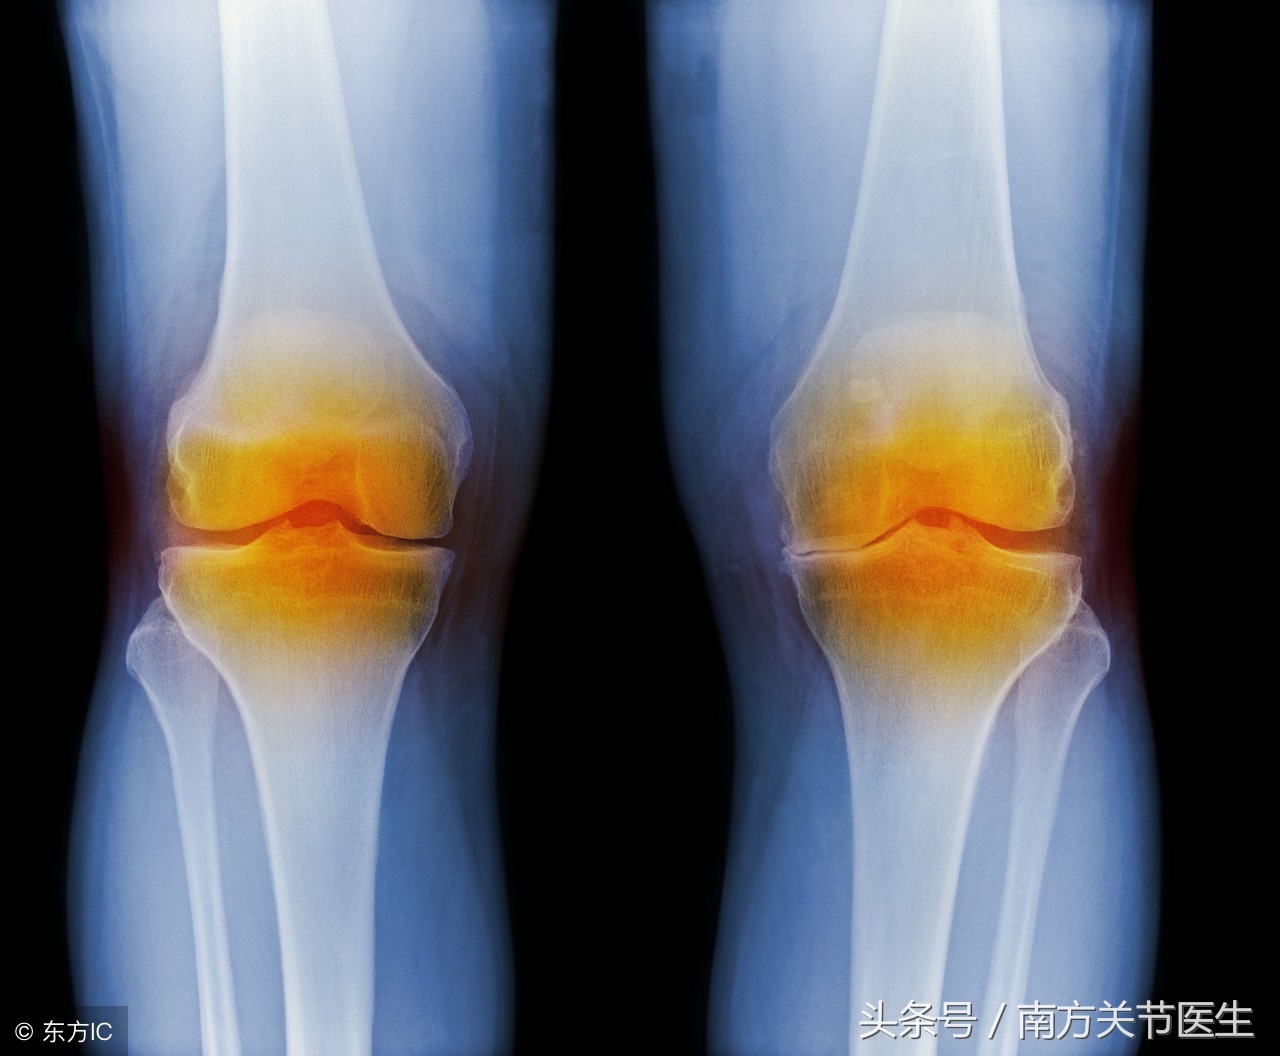

运动后感觉到关节酸痛,这种情况相信很多人都经历过。不过,遇到这种情况时,大部分人会觉得缓一缓就会恢复正常,酸痛感会消失,所以不放在心上。但是,需要知道的是,关节酸痛可能是韧带、软骨等出现了问题,如果放任不管,可能会造成不可逆的损伤的。那么,运动后感觉关节酸痛应该怎么办呢?

膝关节酸痛可能是由于运动时对髌骨和半月板的冲击引起的。如果大腿肌肉能强壮些,则可以对膝关节起到一定的保护作用。也可能是髂胫束的问题引起酸痛的,这与扩筋膜张肌有关。所以有必要锻炼大腿肌肉。